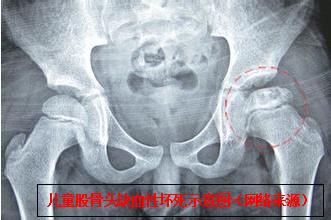

该团队相关负责人介绍,该患儿如不及时快速准确将脱位的髋关节整复,会引发并发症,进而导致股骨头缺血性坏死、髋关节生长紊乱、神经损伤、复发性脱位、创伤后骨关节炎、骨化性肌炎、股骨头创伤性分离。而其中最危急,要与时间赛跑的就是股骨头缺血性坏死,所以,必须在伤后24 小时内完成脱位髋关节的复位。